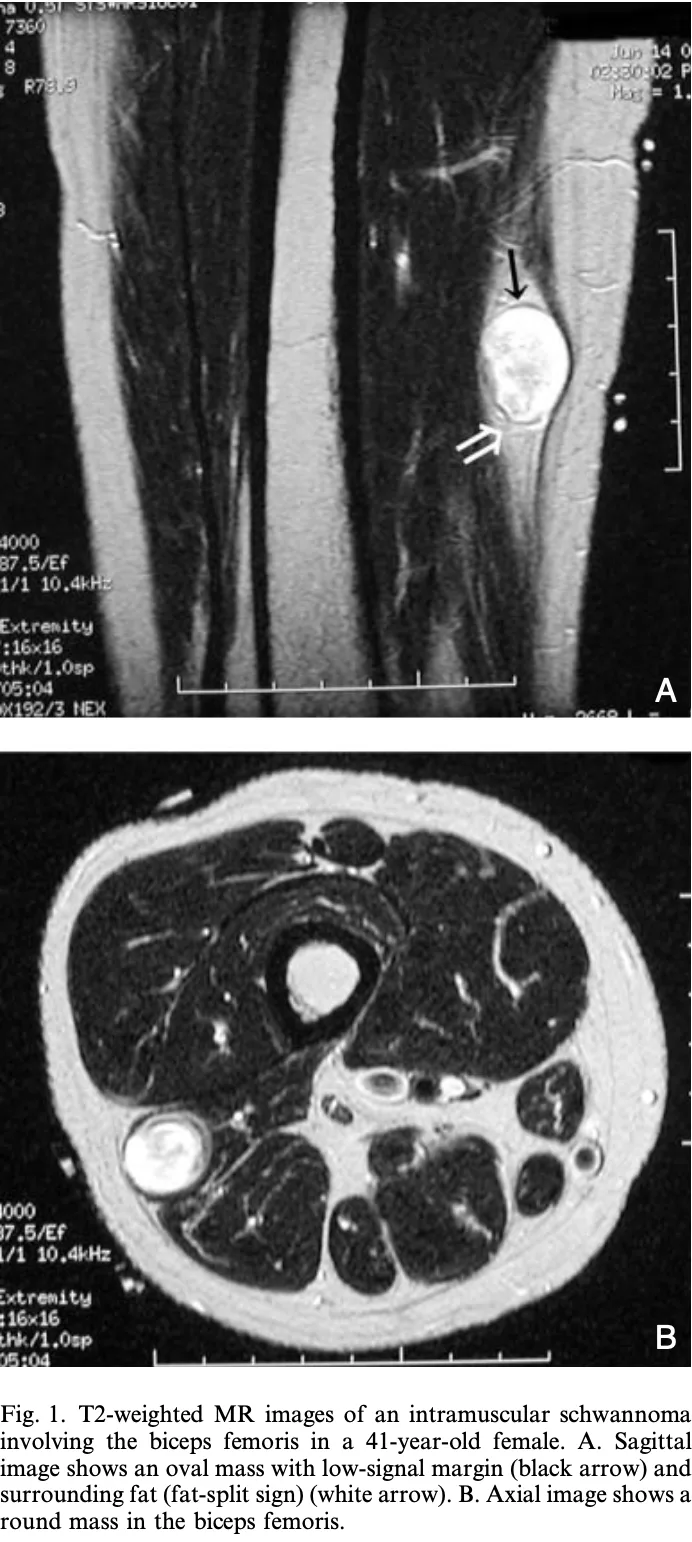

大腿二頭筋の筋肉内神経鞘腫のMRI.

引用元:Shimose S. Major-nerve schwannomas versus intramuscular schwannomas. Acta Radio. 2007. 48.

筋肉内に発生する神経鞘腫は, 神経鞘腫の2 %程度とまれな病態で, 痛みがないのが特徴です.

主幹神経から発生する神経鞘腫のように, 手術によって麻痺を生じる危険性が少ないため, 局所麻酔で核出することにしました.